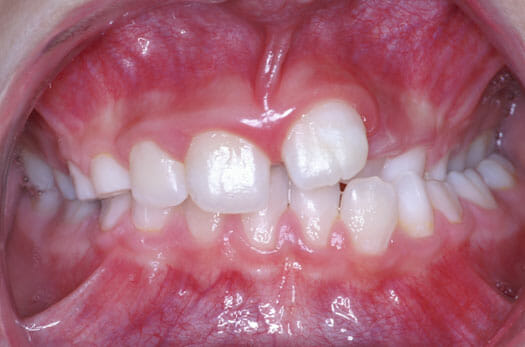

Dès l’âge de 7 à 8 ans, un enfant qui présente un des signes suivants peut être vu en consultation orthodontique.

Tout enfant présentant un des signes suivants peut être vu en consultation orthodontique afin d’établir un diagnostic et proposer un traitement interceptif de phase I le cas échéant.

Il est toujours souhaitable que le patient présente les 8 incisives et les premières molaires permanentes afin de maximiser l’intervention thérapeutique à cet âge.